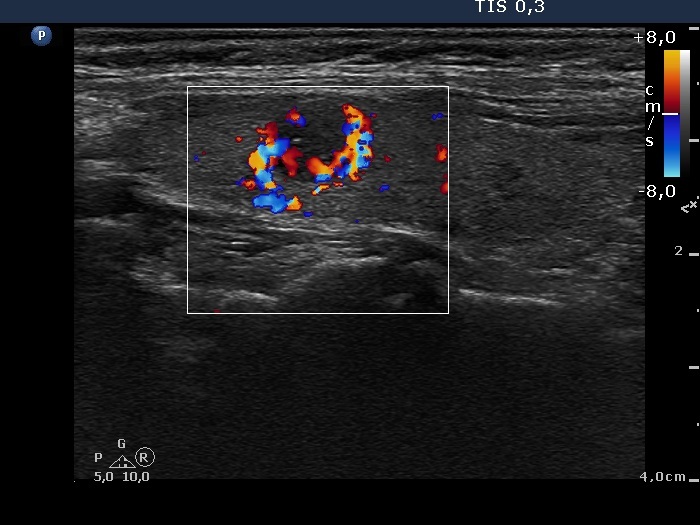

Oxyphilic adenoma - Case 6. (ultrasonographic picture 5)

Right lobe, longitudinal scan, color Doppler mode. This vascular pattern is suspicious.